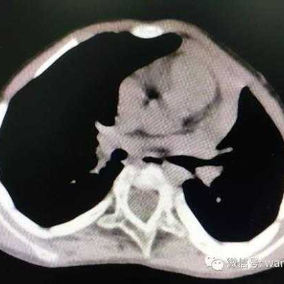

Preoperative Examination

The patient exhibits a noticeable protrusion of the chest wall and a loss of normal spinal curvature, resulting in a visibly unbalanced appearance. He was eventually diagnosed with flatback syndrome combined with a convex deformity of the chest wall.